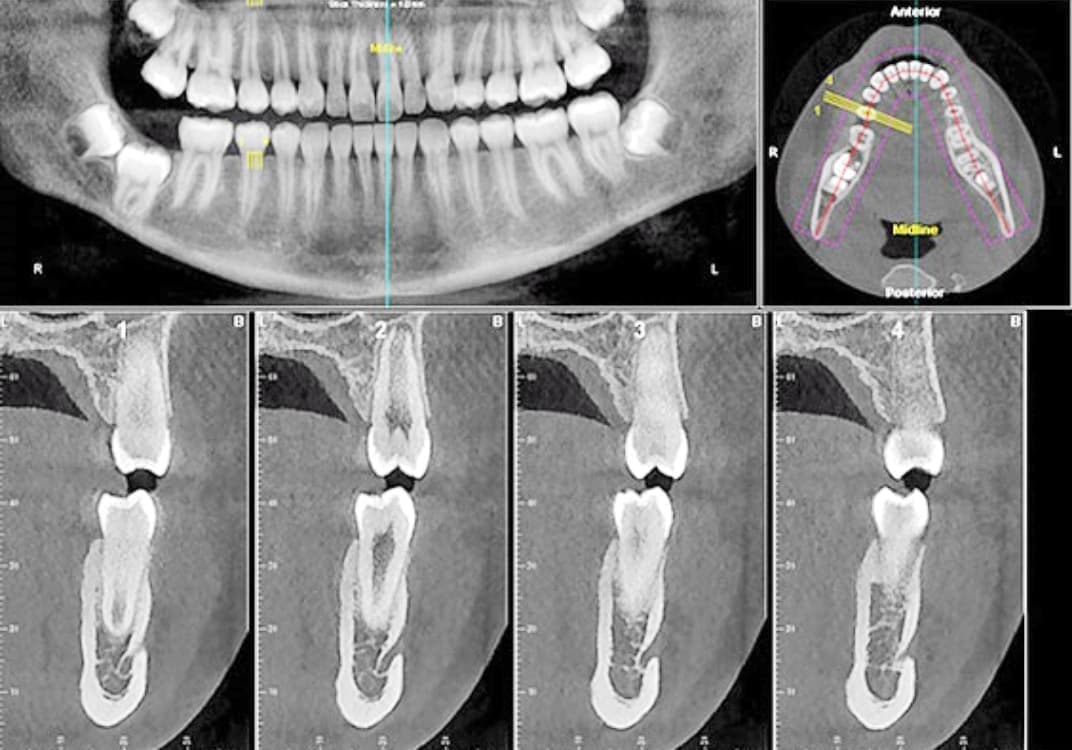

CT 3D デジタルレントゲン

HCT 3D Roentgen

img_4253.jpg ctga_20201009231644597.jpg di3d.jpg

高精細で被爆量も少なく安心

当院では、歯科用CT3Dデジタルレントゲンを活用し、身体への負担を少なく、状況を詳しく把握し、的確な治療を提供出来るよう心掛けております。

CTデジタルレントゲンに使われているX線センサーは高感度で照射時間も短く、より低線量でのレントゲン画像の取得が可能となり、お子様にも安心です。

インプラント手術や歯周病治療、歯列矯正治療、歯の根の病気に関係する治療の正確な診断、治療計画には、3DCTによる撮影が欠かせません。

例えば、親知らずの抜歯や骨内に埋伏している過剰歯の抜歯等、正確な位置や神経や血管等との距離を3次元的に把握することで負担の少ない安心な処置が行えます。